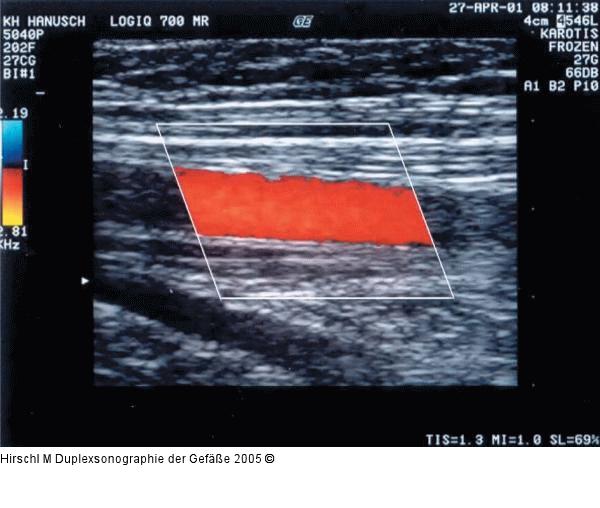

Abbildung 12: Duplexsonographie - Farbfenstereinstellung

Richtig eingestellter Farbfensterwinkel mit dem nun gut farbgefüllten Gefäß. |